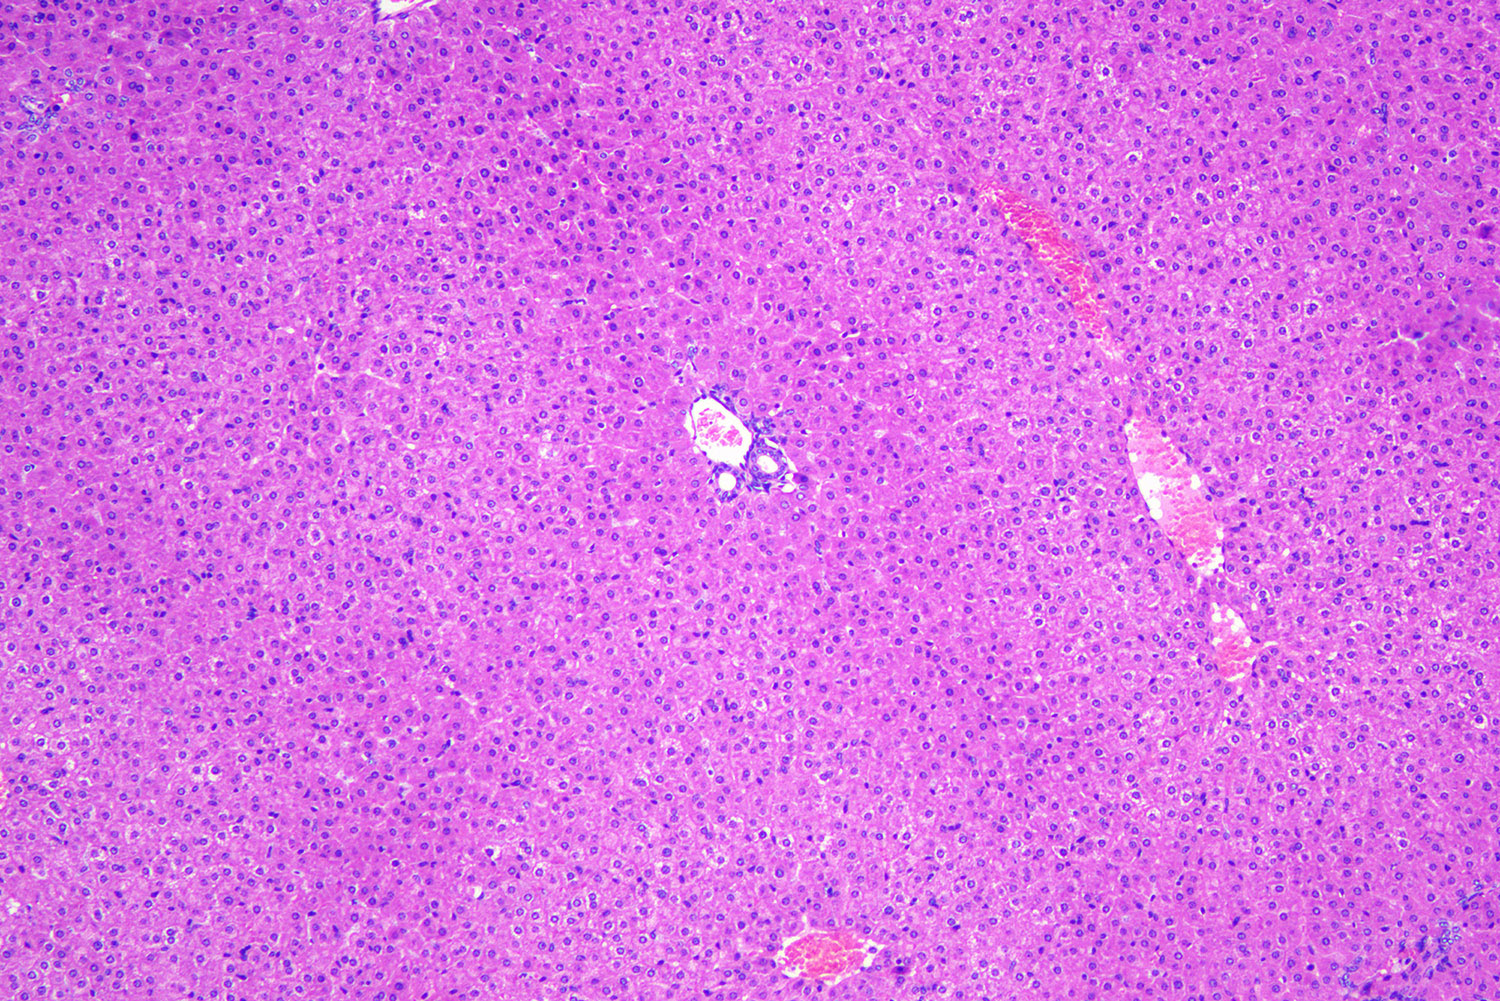

常规染色或HE(Haematoxylin and eosin)染色。它是病理技术中常用的一种方法,通过它可以做出病理诊断和发现寻求别的辅助方法,以达到准确,完整的病理诊断。苏木精染液为碱性 ,主要使细胞核内的染色质与胞质内的核糖体着紫蓝色 ;伊红为酸性染料 ,主要使细胞质和细胞外基质中的成分着红色 。HE染色法是组织学、胚胎学、病理学教学与科研中基本、使用广泛的技术方法。

HE染色步骤:一般包含取材固定,脱水透明,浸蜡包埋,切片与贴片,脱蜡染色,脱水透明,封固等步骤。